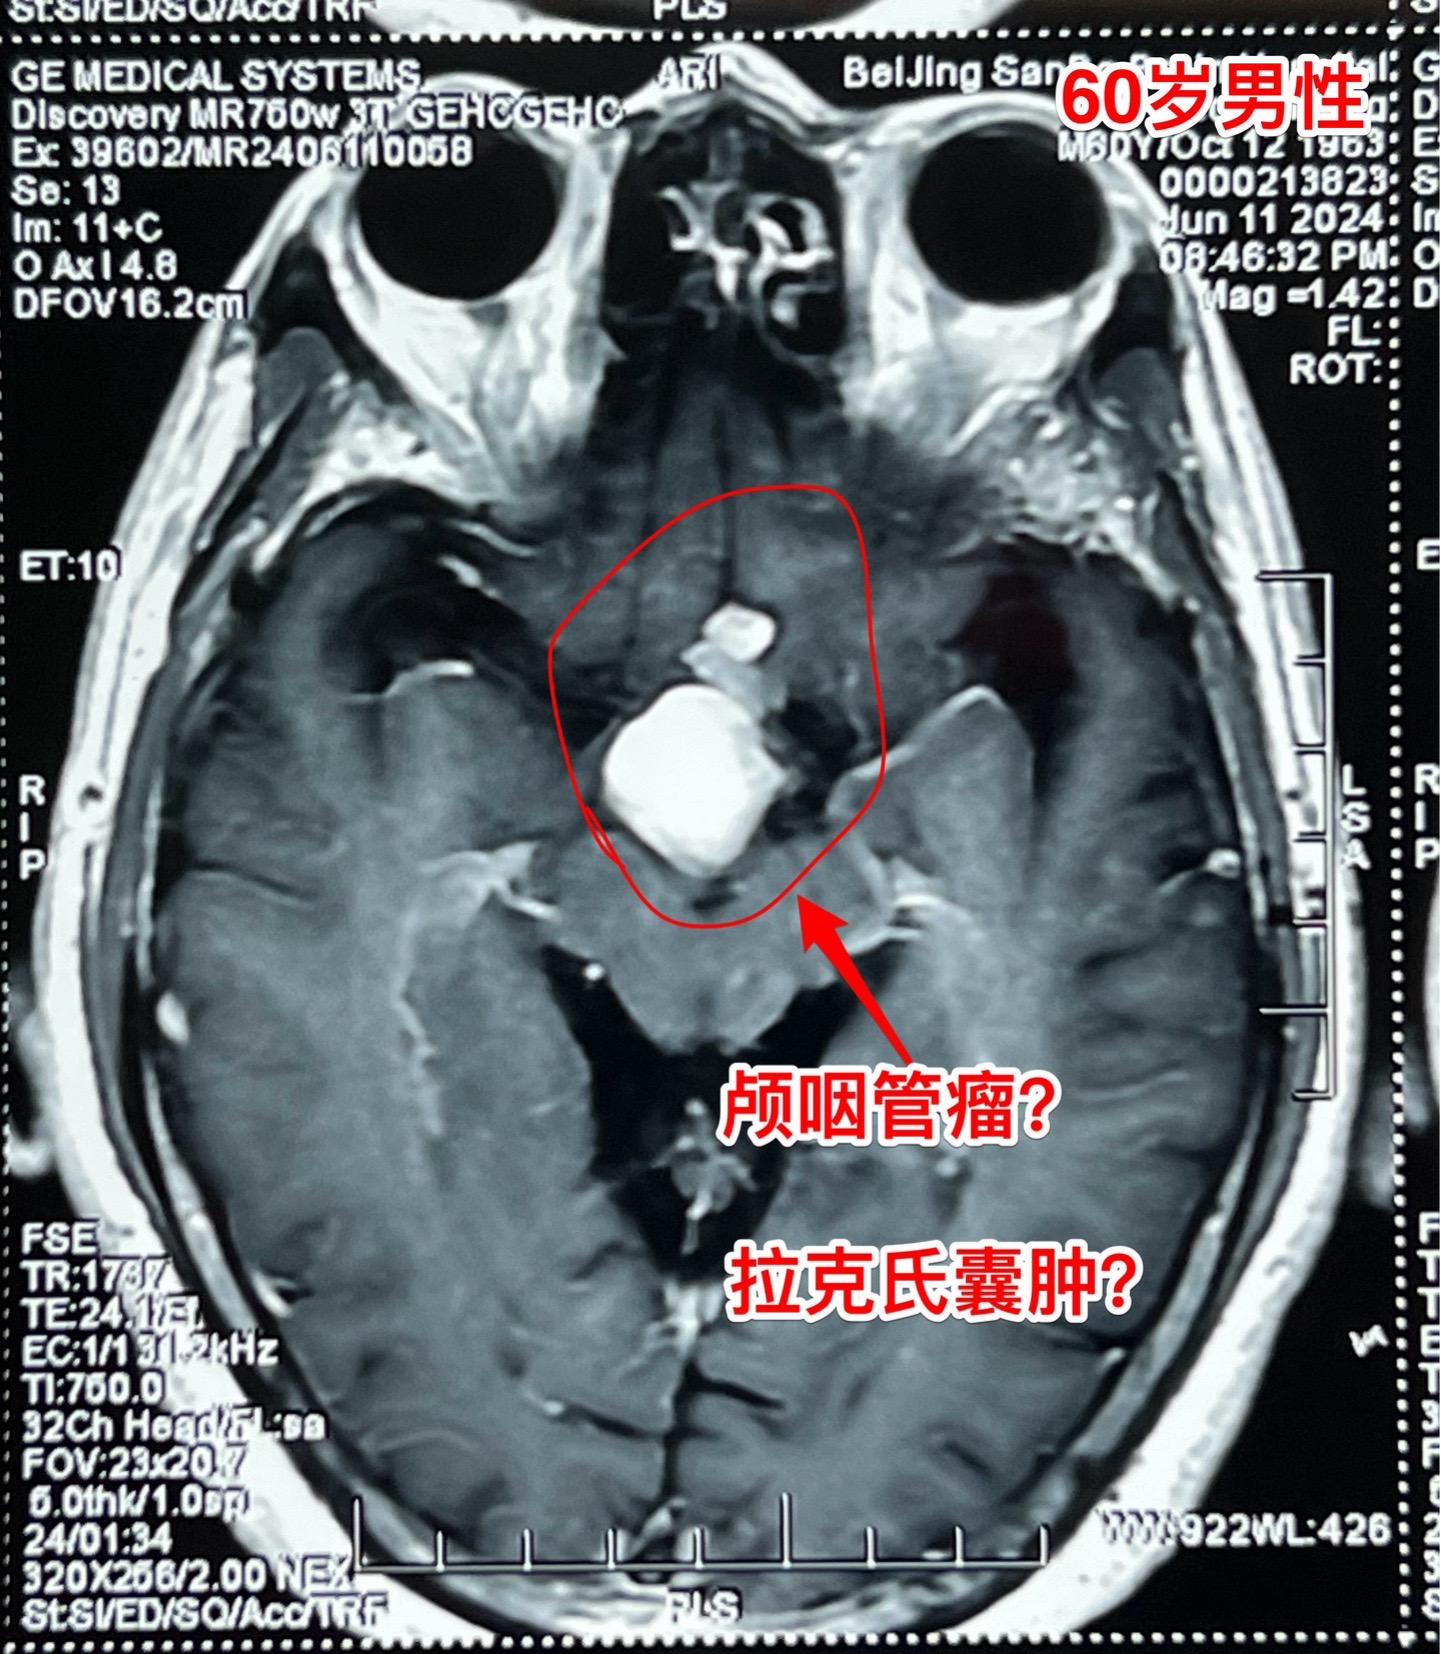

颅咽管瘤与拉克氏囊肿的鉴别不容易。60岁男性,偶然因头痛作体检发现鞍区肿瘤,怀疑为颅咽管瘤。病人无明显的视力下降。肿瘤体积不小了,CT也没有看见钙化。 到底是颅咽管瘤还是拉克氏囊肿? 2024年6月17日作了开颅手术。手术中看见病灶呈囊性,囊壁边界清楚,内有胆固醇结晶体,其周围脑实质有黄染。垂体柄得到保留。 手术后病理报告为:拉克氏囊肿。颅咽管瘤拉克氏囊肿